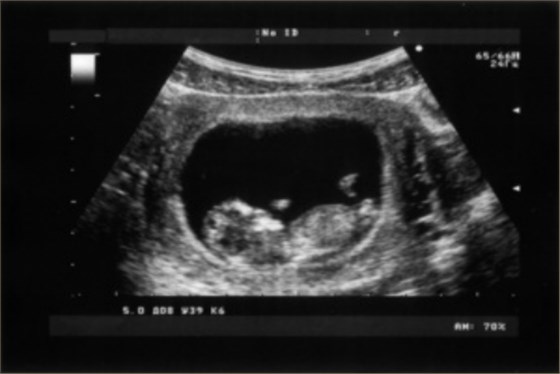

孕晚期超聲不詳細,通常可以檢查胎兒的大小、胎盤、羊水等情況。超聲檢查是婦產(chǎn)科常用的輔助檢查方法,可以利用超聲對妊娠早期、中期的形態(tài)學(xué)檢查進行有效判斷,從而評估胎兒的發(fā)育狀況。

1、胎兒的大小:通過超聲檢查測量胎兒的雙頂徑、頭圍、腹圍以及股骨長等指標(biāo),可以評估胎兒體重。如果胎兒過大,通常與孕婦血糖高、妊娠期糖尿病等有關(guān)。如果胎兒過小,可能與孕周計算不準、營養(yǎng)不良有關(guān);

2、胎盤:超聲檢查胎盤,可以評估胎盤的成熟度,胎盤分為I級、II級、III級,正常胎盤應(yīng)為I級,表示胎盤功能正常。如果胎盤發(fā)生鈣化,則可能出現(xiàn)胎盤老化,如果胎盤達到III級,可能出現(xiàn)胎盤早剝、前置胎盤等情況;

3、羊水:通過超聲檢查羊水情況,可以判斷胎兒的生長發(fā)育情況以及羊水量是否正常。如果羊水較多,說明胎兒的尿液生成增多,可能是由于胎兒憋尿引起。如果羊水較少,可能是由于胎膜早破、妊娠期高血壓等情況引起;

4、臍帶:通過超聲檢查臍帶,可以觀察臍帶的長度、周數(shù)、位置以及臍帶內(nèi)血管的情況,從而判斷是否存在臍帶繞頸以及臍帶扭轉(zhuǎn)等情況。如果存在臍帶繞頸或者臍帶扭轉(zhuǎn),可能會影響胎兒血液以及氧氣的供應(yīng),需進行相應(yīng)處理。

除上述檢查外,還可以看胎位是否正常。通過超聲檢查判斷胎位是否異常,還可以對前置胎盤、臀位等異常胎位進行矯正。通過超聲檢查明確診斷后,需要根據(jù)醫(yī)生建議選擇合適的分娩方式。孕婦進行分娩之前,應(yīng)放松心情,避免過于害怕、焦慮,因為分娩是較為痛苦的過程。